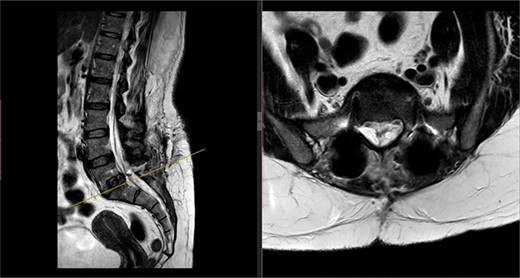

Postoperatively, the patient developed severe radiculopathy down the left leg and required opiates. The patient could not move the left leg and was unable to mobilize. X-rays showed the implants were in position (Fig. 3), but the information from a fresh MRI scan was limited due to metal artefact (Fig. 4). With ongoing, unrelenting pain, she was returned to theatre on the fourth postoperative date, and the wound was re-explored. Intraoperatively, no dural tear was identified, the nerve roots were free, and the screws appeared in position. She was then discharged home after ten nights in hospital, instead of the standard three nights that would be common practice.

Postoperative MRI of the lumbar spine performed in January 2017. Interference from the metallic pedicular screws limited the scans clarity.